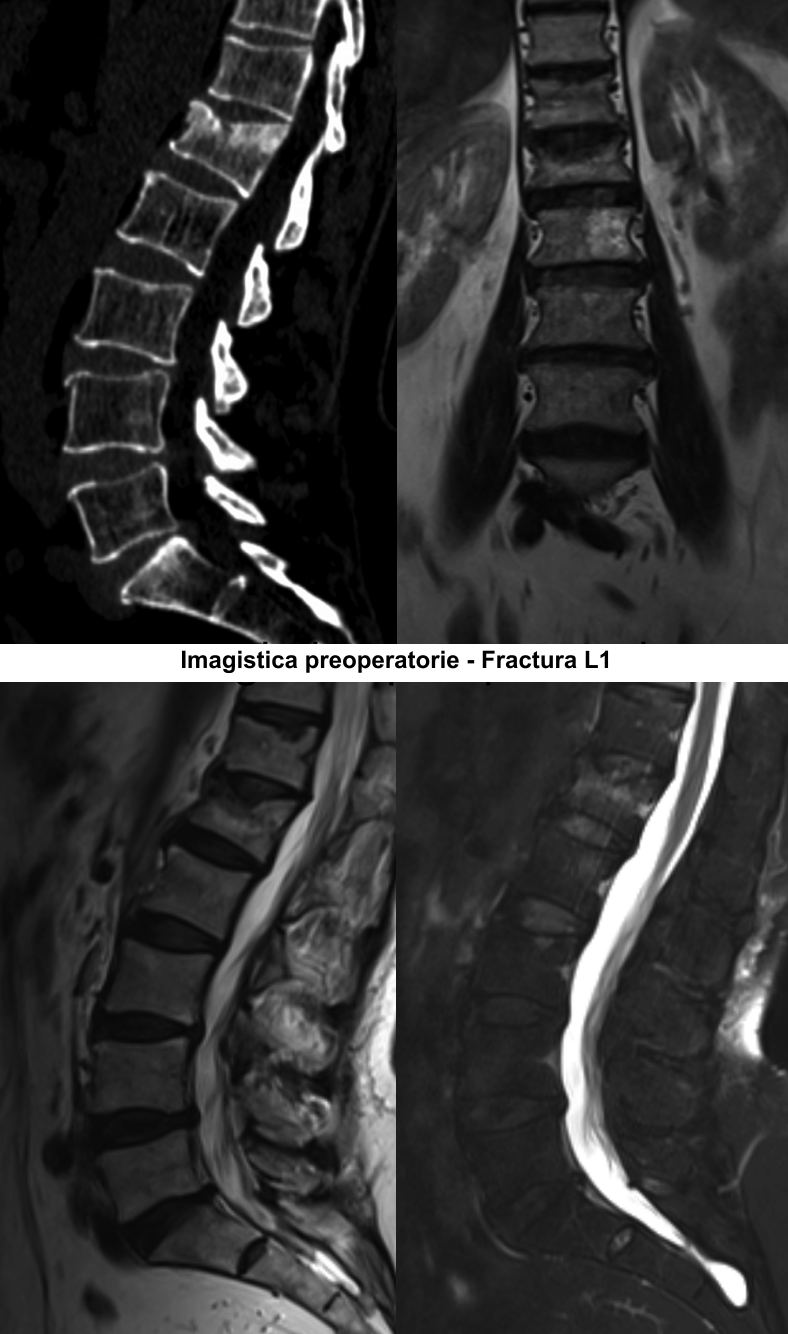

În urma investigaţiilor imagistice prin CT şi IRM a coloanei lombare, a fost stabilit diagnosticul Fractură tasată a corpului vertebral LI gr.II şi Hemangiom agresiv al hemicorpului vertebral LII pe stânga. Luând în considerare datele clinice şi paraclinice, s-a decis de a trata simultan aceste două vertebre, prin combinarea a două tehnici chirurgicale minim invazive – vertebroplastia percutanată şi kyfoplastia cu baloane expandabile.

Vertebroplastia percutanată (VTP) reprezintă injectarea unui ciment acrilic (metilmetacrilat) în vertebra patologic modificată sub control fluoroscopic sau tomografic. Această tehnică a fost propusă în 1984 de către neurochirurgul francez Pierre Galibert pentru tratamentul preoperator al unui hemangiom agresiv de vertebră cervicală, pentru a diminua hemoragia intraoperatorie. Ulterior, vertebroplastia a fost propusă pentru tratamentul fracturilor vertebrale osteoporotice şi în metastazele vertebrale cu sindrom algic pronunţat.

Majoritatea fracturilor vertebrale au loc în segmentul toracic inferior sau lombar superior şi sunt cauzate de traumatisme, osteoporoză sau tumori ale coloanei vertebrale. Scopul operaţiei este de a „întări” vertebra fracturată cu ciment special predestinat acestor scopuri. Vertebra în care a fost introdus cimentul devine mai rigidă, mai stabilă, iar în urma acestui fapt are loc diminuarea semnificativă a durerilor preoperatorii. Eficienţa tratamentului prin vertebroplastie şi kyfoplastie este de peste 90% în funcţie de tipul şi localizarea fracturii vertebrale. Acest tip de operaţii este unul sigur, poate fi aplicat pacienţilor în vîrstă, care suferă cel mai frecvent de osteoporoză, iar rata complicaţiilor se situează sub 1%.